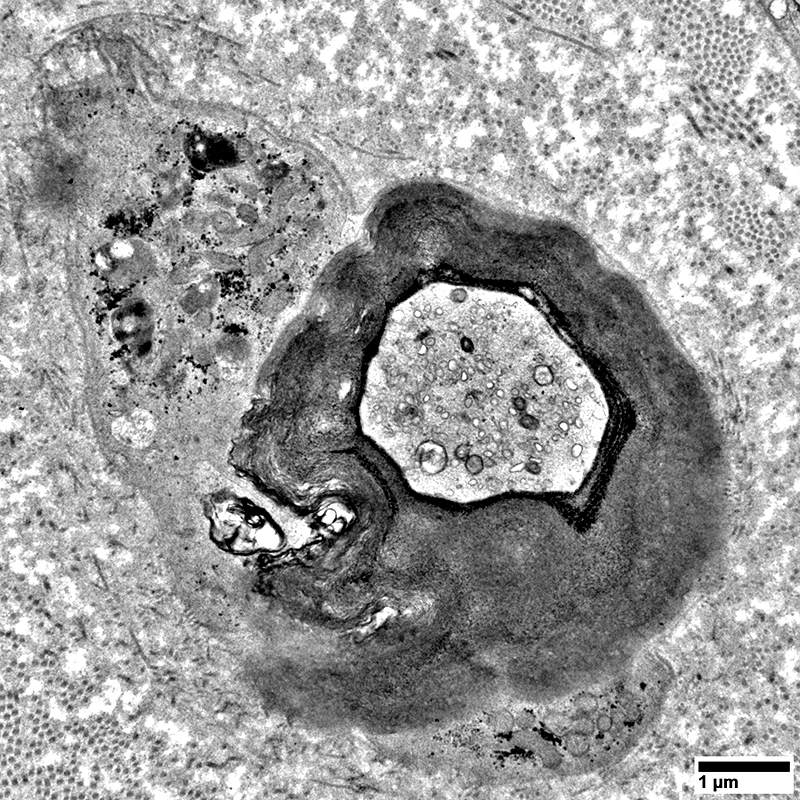

Myelin Damage & Ovoids

Schwann Cells

Some contain Lipid debris

From: R Schmidt

Myelin Damage: Lipid Droplets & Ovoids in Schwann cells